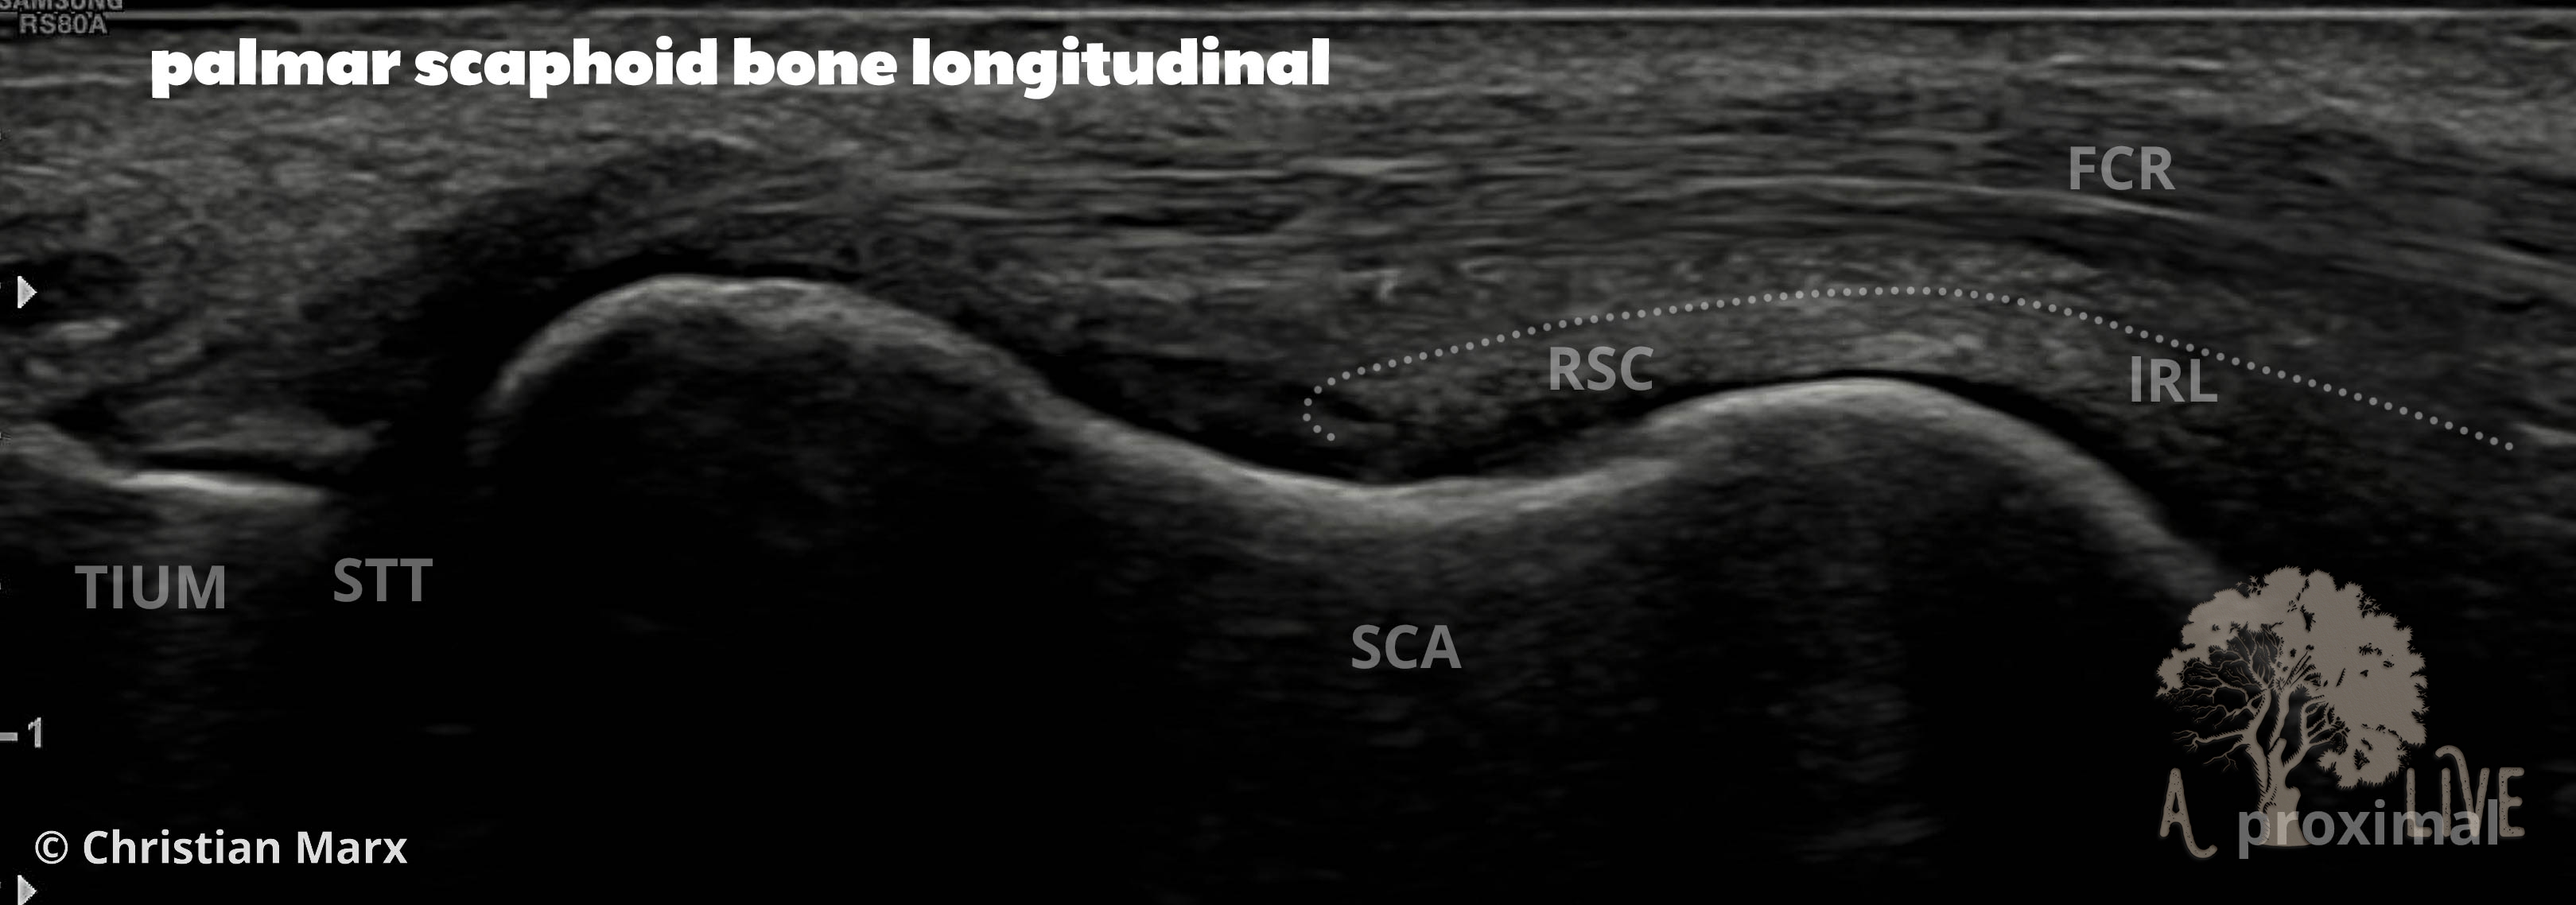

carpal ligaments